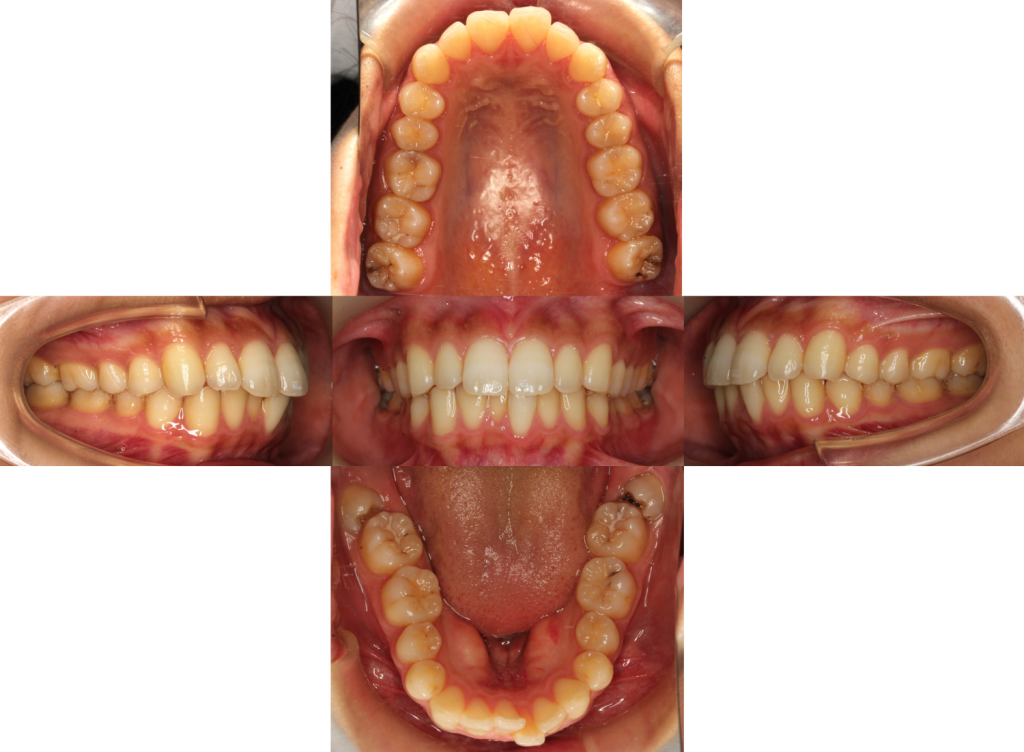

矯正前の口腔内の状態です。

下の歯のガタツキと口元の突出感をお悩みでカウンセリングにいらっしゃいました。